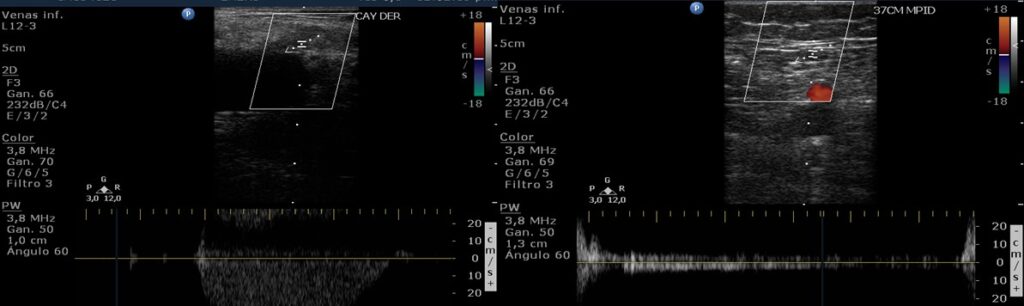

La evaluación comienza desde la región inguinal, utilizando un transductor lineal con una frecuencia de 7-11MHz. En modo B se visualiza la unión safeno-femoral y, realizando un corte longitudinal, se mide el diámetro anteroposterior del cayado, situado entre la válvula ostial y preostial (Fig. 16). Posteriormente se le solicita al paciente que realice la maniobra de Valsalva o se comprime la región gemelar y se valora mediante DC para corroborar la adecuada competencia valvular. Así se continúa el estudio, con cortes transversos y siguiendo el recorrido de la vena safena mayor, las tributarias y las venas perforantes, realizando compresiones distales cada 3 a 5 cm (Fig. 17).